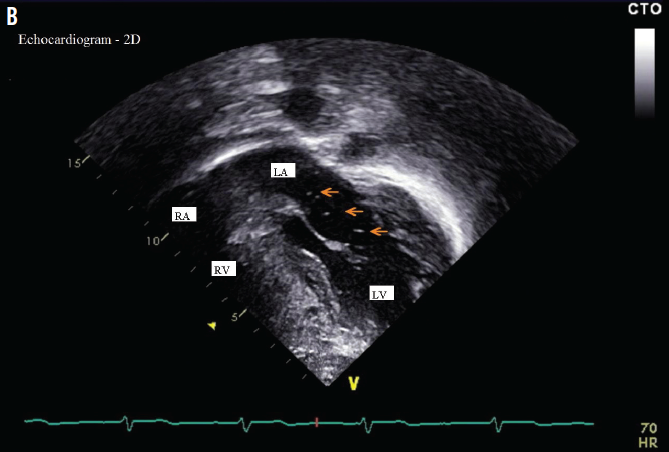

Rhabdomyoma

01/26/2016

Magda Mendez, MD, FAAP; Sergey Prokhorov, MD; Julissa Garrido-Joyce, MD; Eduardo Garrido, MD

A 28-year-old woman with no remarkable personal or family history gave birth to a full-term, large-for-gestational-age boy via cesarean delivery.